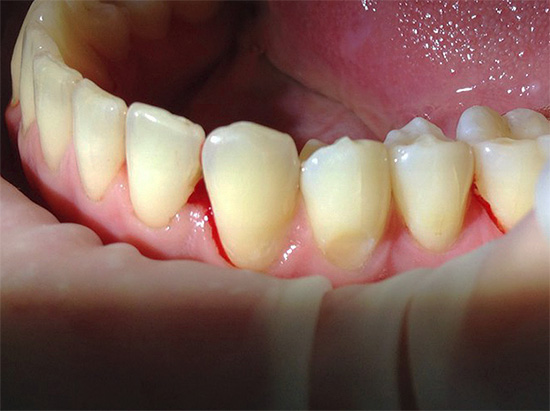

Con la posizione aperta della carie di cemento sui denti anteriori in combinazione con la carie cervicale, di norma, già allo stadio di un punto cariato senza una cavità cariata e nessun sintomo, si possono sospettare seri problemi e consultare un medico. Inoltre, in questo caso stiamo parlando della comodità di comunicare con i propri cari, amici, colleghi e altre persone. La comparsa di punti scuri, una sfumatura gessosa di smalto, le sue crepe e le schizzi al bordo con la gomma consentono di determinare la carie di cemento nella fase iniziale di sviluppo, quando può ancora "sfondare" nell'area subgengivale.

Con estese cavità carie che si estendono dalla superficie esterna del dente più in profondità nelle gengive, si verificano solitamente reazioni a freddo, caldo, dolce, acido, nonché una sensazione di indolenzimento, dolore durante il cibo. Spesso la gomma si allontana dal dente così tanto che sotto di esso è visibile l'area interessata del cemento radicolare e la radice stessa. In tali casi, è necessario consultare immediatamente uno specialista per ulteriori studi e conferma della diagnosi.